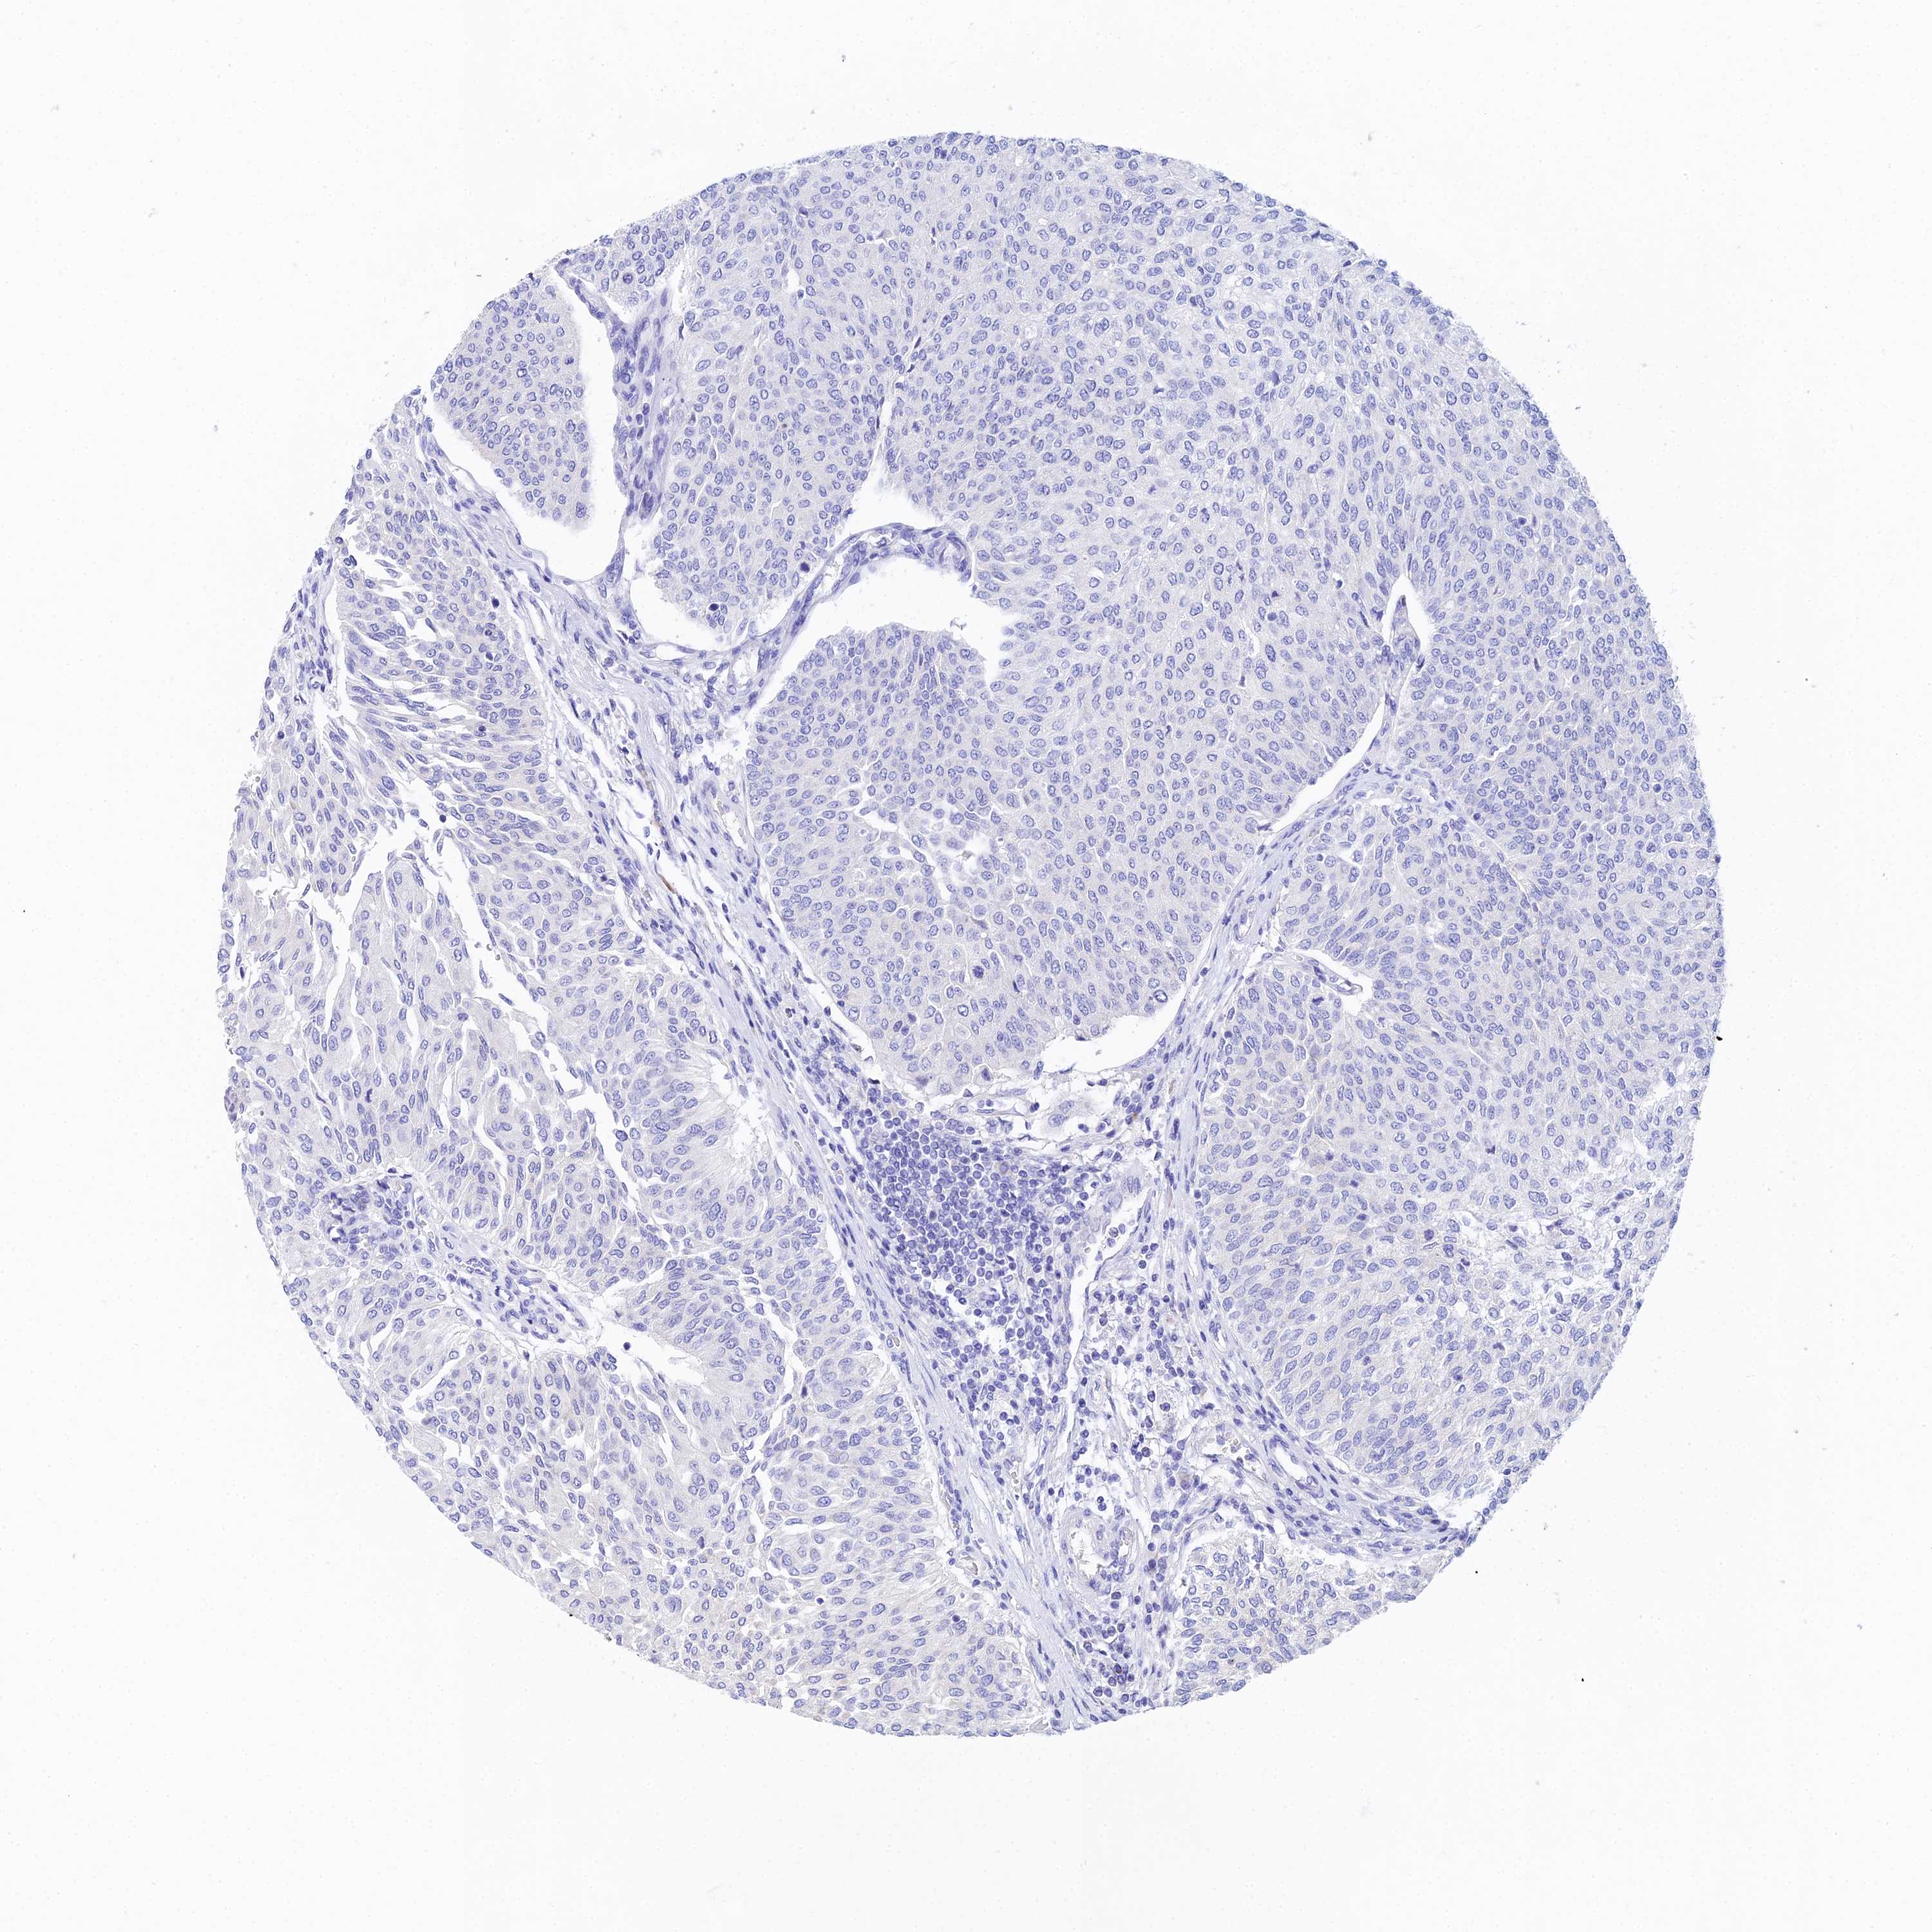

UROTHELIAL CANCER - Protein expressioni

A mouse-over function shows sample information and annotation data. Click on an image to view it in a full screen mode. Samples can be filtered based on level of antibody staining by selecting one or several of the following categories: high, medium, low and not detected. The assay and annotation is described here.

Note that samples used for immunohistochemistry by the Human Protein Atlas do not correspond to samples in the TCGA dataset.

Antibody stainingi

Antibody staining in the annotated cell types in the current human tissue is reported as not detected, low, medium, or high, based on conventional immunohistochemistry profiling in selected tissues. This score is based on the combination of the staining intensity and fraction of stained cells.

Each image is clickable and will lead to virtual microscopy that enables deeper exploration of all samples and also displays staining intensity scores, fraction scores and subcellular localization as well as patient and tissue information for each sample.

Antibody HPA024090

Staining

High

Medium

Low

Not detected

Intensity

Strong

Moderate

Weak

Negative

Quantity

>75%

75%-25%

<25%

None

Location

Nuclear

Cytoplasmic/membranous

Cytoplasmic/membranous,nuclear

Urothelial carcinoma, High grade

Urothelial carcinoma, Low grade